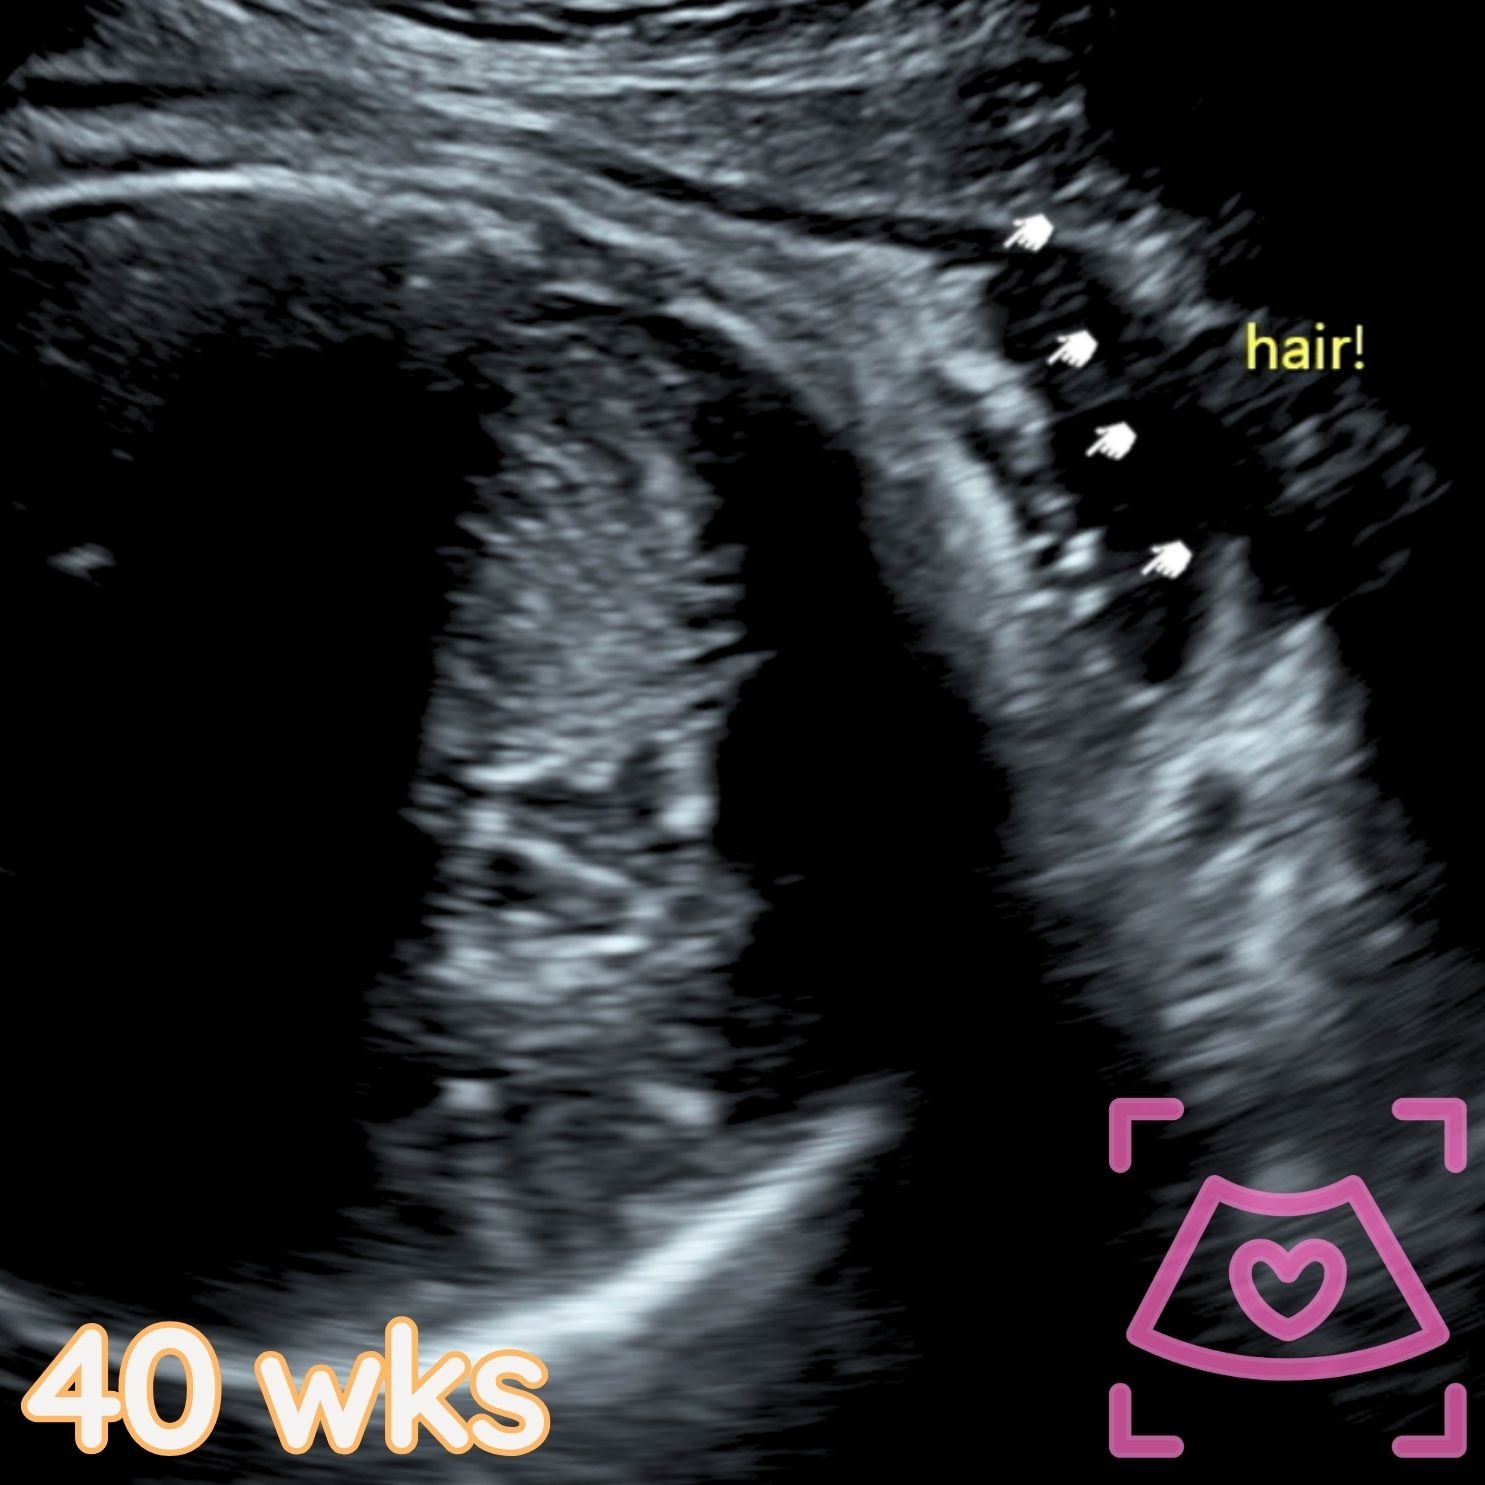

All ultrasounds at this facility are performed abdominally (on top). See examples below from 5-40 weeks! Recommended times can be found on the Services Page and when booking.

3rd Trimester